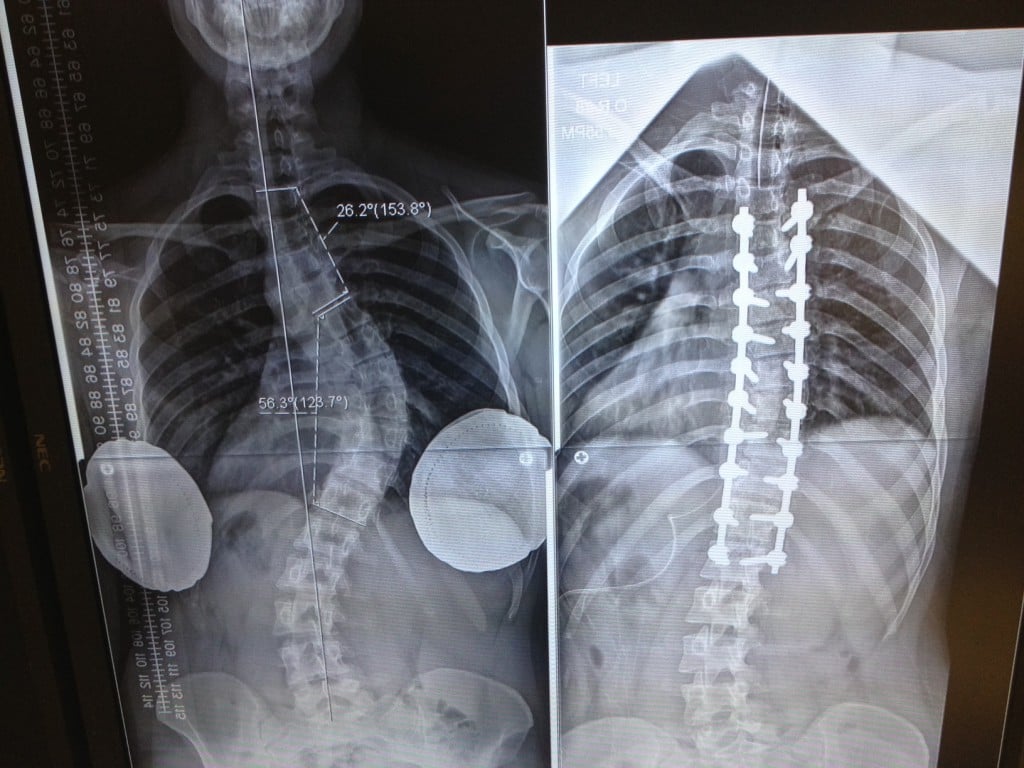

I found out about my scoliosis at the age of 15 when my mother noticed my right shoulder blade was subtly protruding. At the time, my curvature was around 20-30 degrees. We tried every possible non-surgical treatment ranging from physical therapy to wearing a back brace, but nothing worked. As time passed, my curvature was getting worse. At the time, we were not living in the U.S., and each surgeon we visited did not seem confident or competent enough to do the surgery. On top of that, I have Marfan Syndrome, which doctors were not very familiar with but knew would complicate the surgery. Because of this, we decided hold off on any type of surgery.

After I moved to New York for college, my family and I agreed I was in the best place to find a spine surgeon. After seeing a few doctors, I was referred to Dr. Kim. After seeing so many doubtful doctors, it was one of the most relieving experiences having my first appointment with Dr. Kim. Despite my 100+ degree curvature, he was extremely confident that he could perform my surgery. Seeing the extensive research Dr. Kim did in preparation for the surgery assured me that I was in very good hands.

After two months of halo-gravity traction (HGT) pre-surgery, nine hours of spinal fusion surgery, and four months of post-operative recovery, I am now writing this to show my gratitude toward all the doctors, nurses, and office staff at HSS who helped me throughout this process. Even with two more months of post-operative precautions, I am feeling better than I ever had. Just last year, I was convinced I'd have severe scoliosis for the rest of my life. I am forever grateful for what Dr. Kim and his team were able to do for me.